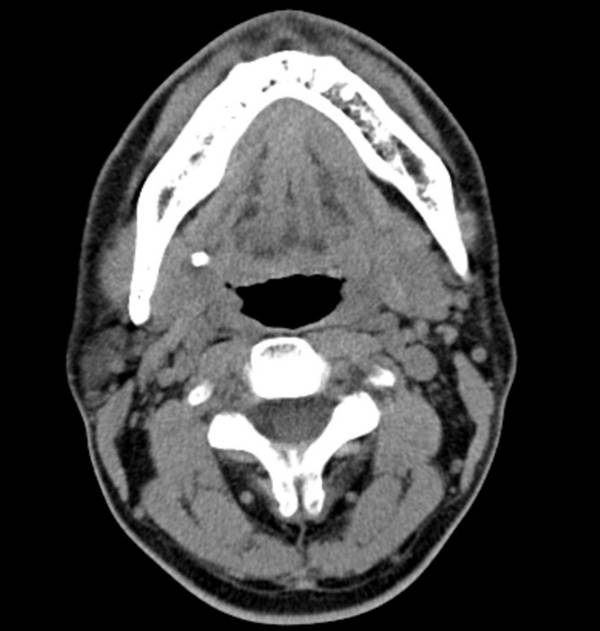

▲턱밑샘 타석증 CT 소견

음식을 먹을 때 턱밑이 부어오르거나 혀 밑이 부어오르고 통증을 느낀다면 타석증을 의심해야 합니다. 타석증이란 침샘에서 침이 분비되어 나오는 침샘관에 돌이 생기는 질환입니다. 침이 나와야 하는 길목을 돌이 막고 있기 때문에 침샘내에 침이 정체되어 분비가 안되어 침샘 부위가 붓고 염증이 생깁니다. 대개 침샘염을 유발하는 가장 흔한 원인으로 타석증을 들 수 있습니다.

정확한 원인은 알 수 없지만 침의 분비가 정체되고, 침샘관 내의 상피의 염증 등으로 인해 침 성분에 포함되어 있는 칼슘염의 침착으로 발생합니다. 대부분의 타석증은 턱밑샘(80%)에 생기고 귀밑샘(19%)이나 다른 침샘(1-2%)에 생기는 경우는 비교적 드뭅니다.

대개 식사 후에 턱밑이 부어오르면서 통증이 반복적으로 생기고 심한 경우에는 침샘관으로 농이 배출되는 경우도 있습니다. 이러한 반복되는 침샘염으로 침샘이 위축되고 침샘관이 협착을 초래하여 만성 침샘염을 유발하기도 합니다.